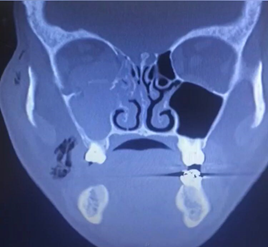

A 42-year-old male patient with a medical history of arterial hypertension and chronic kidney disease undergoing renal replacement therapy, who consulted the Clínica Universidad de La Sabana for a one-day clinical picture of facial trauma secondary to an accidental fall from the stairs who presented edema, ecchymosis and chemosis in the right eye at the physical examination. A computerized axial tomography (CAT) of the paranasal sinuses was performed with findings of a fracture of the roof of the right maxillary sinus and of the orbital floor and additionally, right asymmetric exophthalmos (see Figure 1), associated with hematoma, periorbital subcutaneous emphysema and anterior and inferior perimalar. Therefore, an impure blow-out fracture of the right orbital floor was considered, with an indication for open reduction surgery plus emergency reconstruction of the orbital floor. The patient was taken to a surgical procedure where a transconjunctival approach was performed in the right eye; the inferior rectus muscle was released, achieving decompression of the orbit. A mesh was placed, achieving open reduction of the orbital floor with subsequent reconstruction.

Figure 1 Fracture of the floor of the orbit (black arrowhead), fracture of the medial wall of the orbit (black arrow) and Hemosene (white arrow).